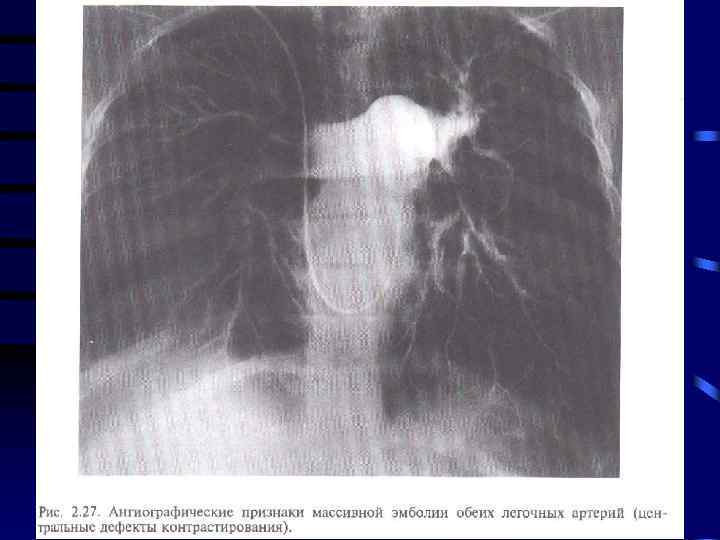

Исходы: 1. При своевременном и адекватном лечении выздоровление 2. Развитие посттромбофлебитического синдрома 3. Тромбоэмболия легочной артерии с развитием инфарктной пневмонии или наступлением внезапной смерти